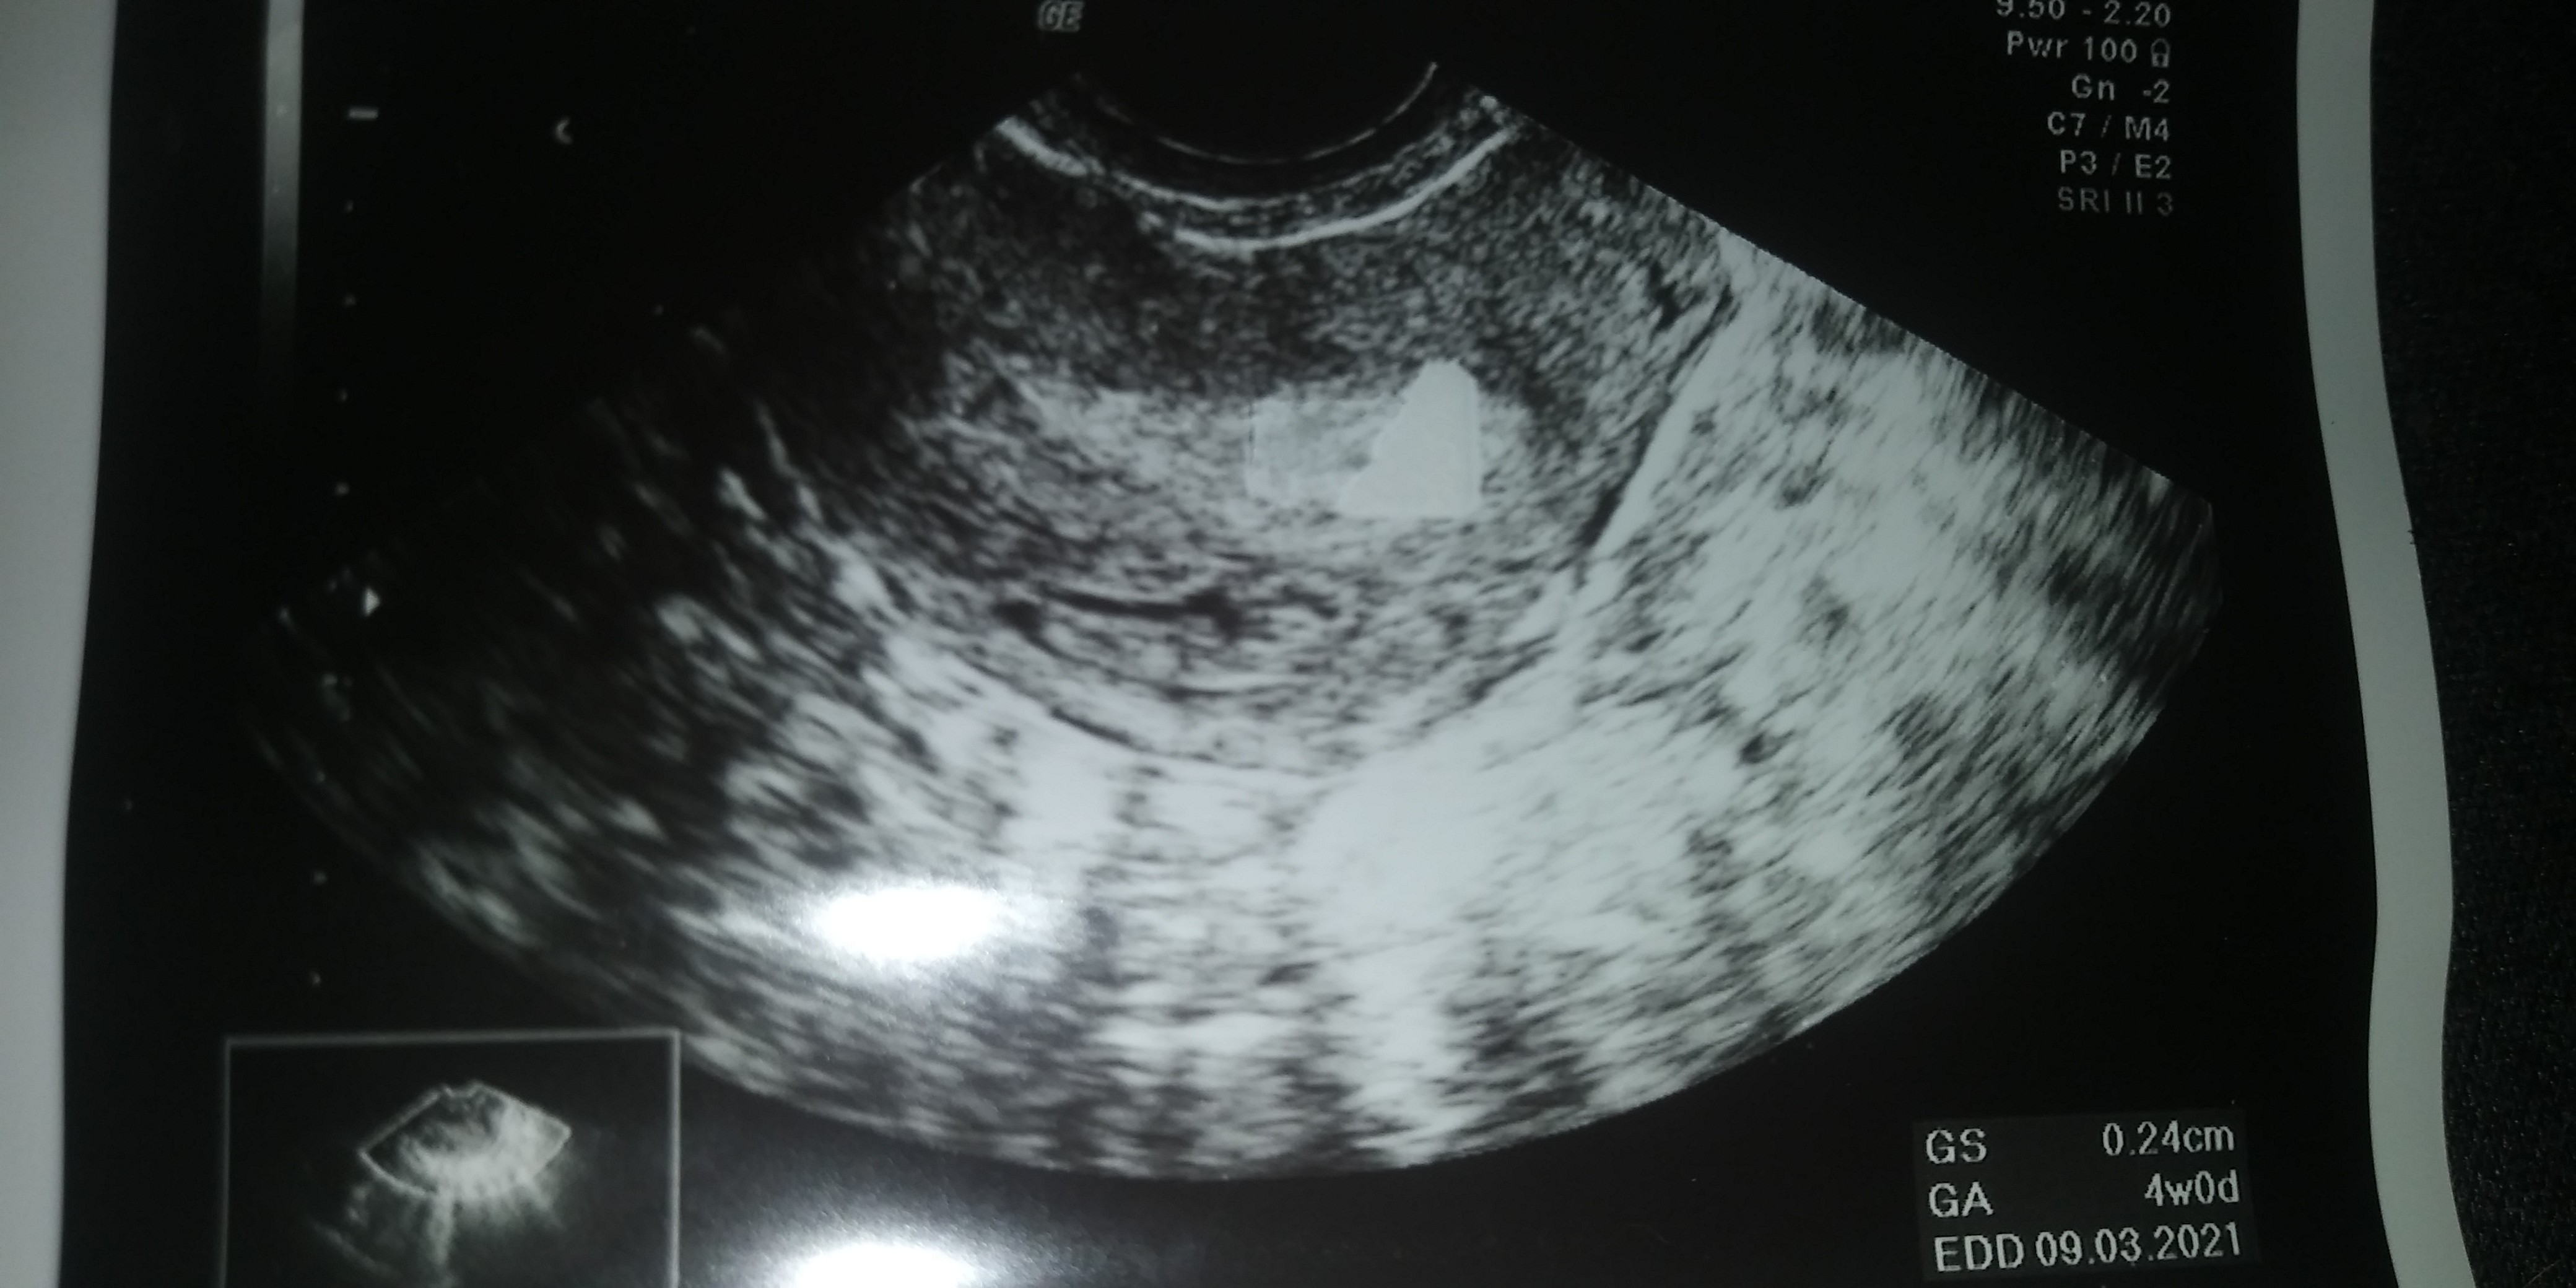

Super miałaś robione USG było już coś widać. Pochwal się 😁 ja mam wizytę w środę ostatni miesiączka 22 maja

W załączniku.z kalkulatora wynika ze moj przyrost to 82 % to duzo ?